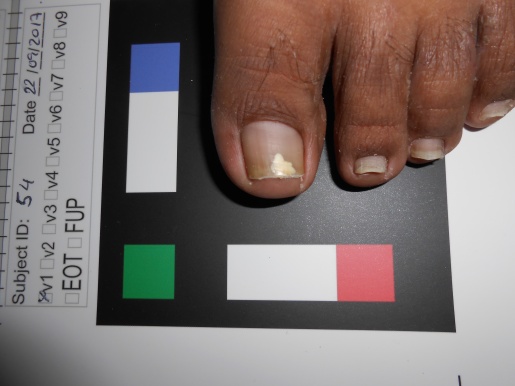

The dataset used in this study was taken in the clinical practice. Following the guidelines of a well-defined medical study, images were acquired in real conditions. All of them were captured in the doctor’s office with their smartphones’ embedded camera. To control some of the environmental conditions, we designed a template to use as the scene background (see Figure 2). During the acquisition process, however, we could not control some other environmental conditions, such as the capture viewpoint the camera setup or the illumination.

The dataset is composed of 348 images of human big toes acquired using the doctor’s cameras attached to off-the-shelf smartphones. A sample image is found in Fig. 8. As previously explained, during the image acquisition stage, some parameters could not be controlled, such as the illumination, the specific capture viewpoint and the camera specifications.